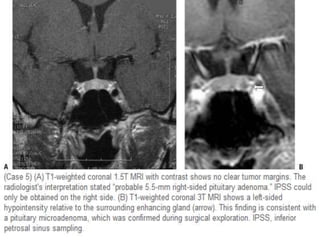

Dynamic MRI contrast images in coronal plane showing a superior contour convexity with a small nodule Figure 3b: Zoomed

images of dynamic MRI, showing the same adenomatous nodule. Note the size of the nodule, which measured two mm.

Coronal T1 and T2WI show microadenoma along the right aspect of the gland which

appears bright at the T2WI.

Post-contrast coronal T1WI shows hypointense microadenoma along the right aspect of the gland.

Delayed sagittal images after 10 minutes shows enhancing microadenoma is more clear.

These images show a classic case: on T1 a lesion about 3-4 mm in diameter, slightly hypointense compared to

normal pituitary tissue, located in the pituitary gland. On T2, the lesion is slightly hyperintense. The

sensitivity of an unenhanced MRI scan for detecting pituitary microadenomas is about 70%.

On an unenhanced scan, approximately 70% of all pituitary macroadenoma can be detected.

If you give gadolinium, you can reduce the false-negative rate from 30% to 15%.

As mentioned earlier, this usually does not affect patient management.

Coronal T1 and T2-weighted images and T1-weighted images before and after gadolinium. In

this patient the lesion in the pituitary gland is only detectable after the administration of

intravenous contrast. The differential diagnosis: pituitary microadenoma or Rathke's cleft cyst.